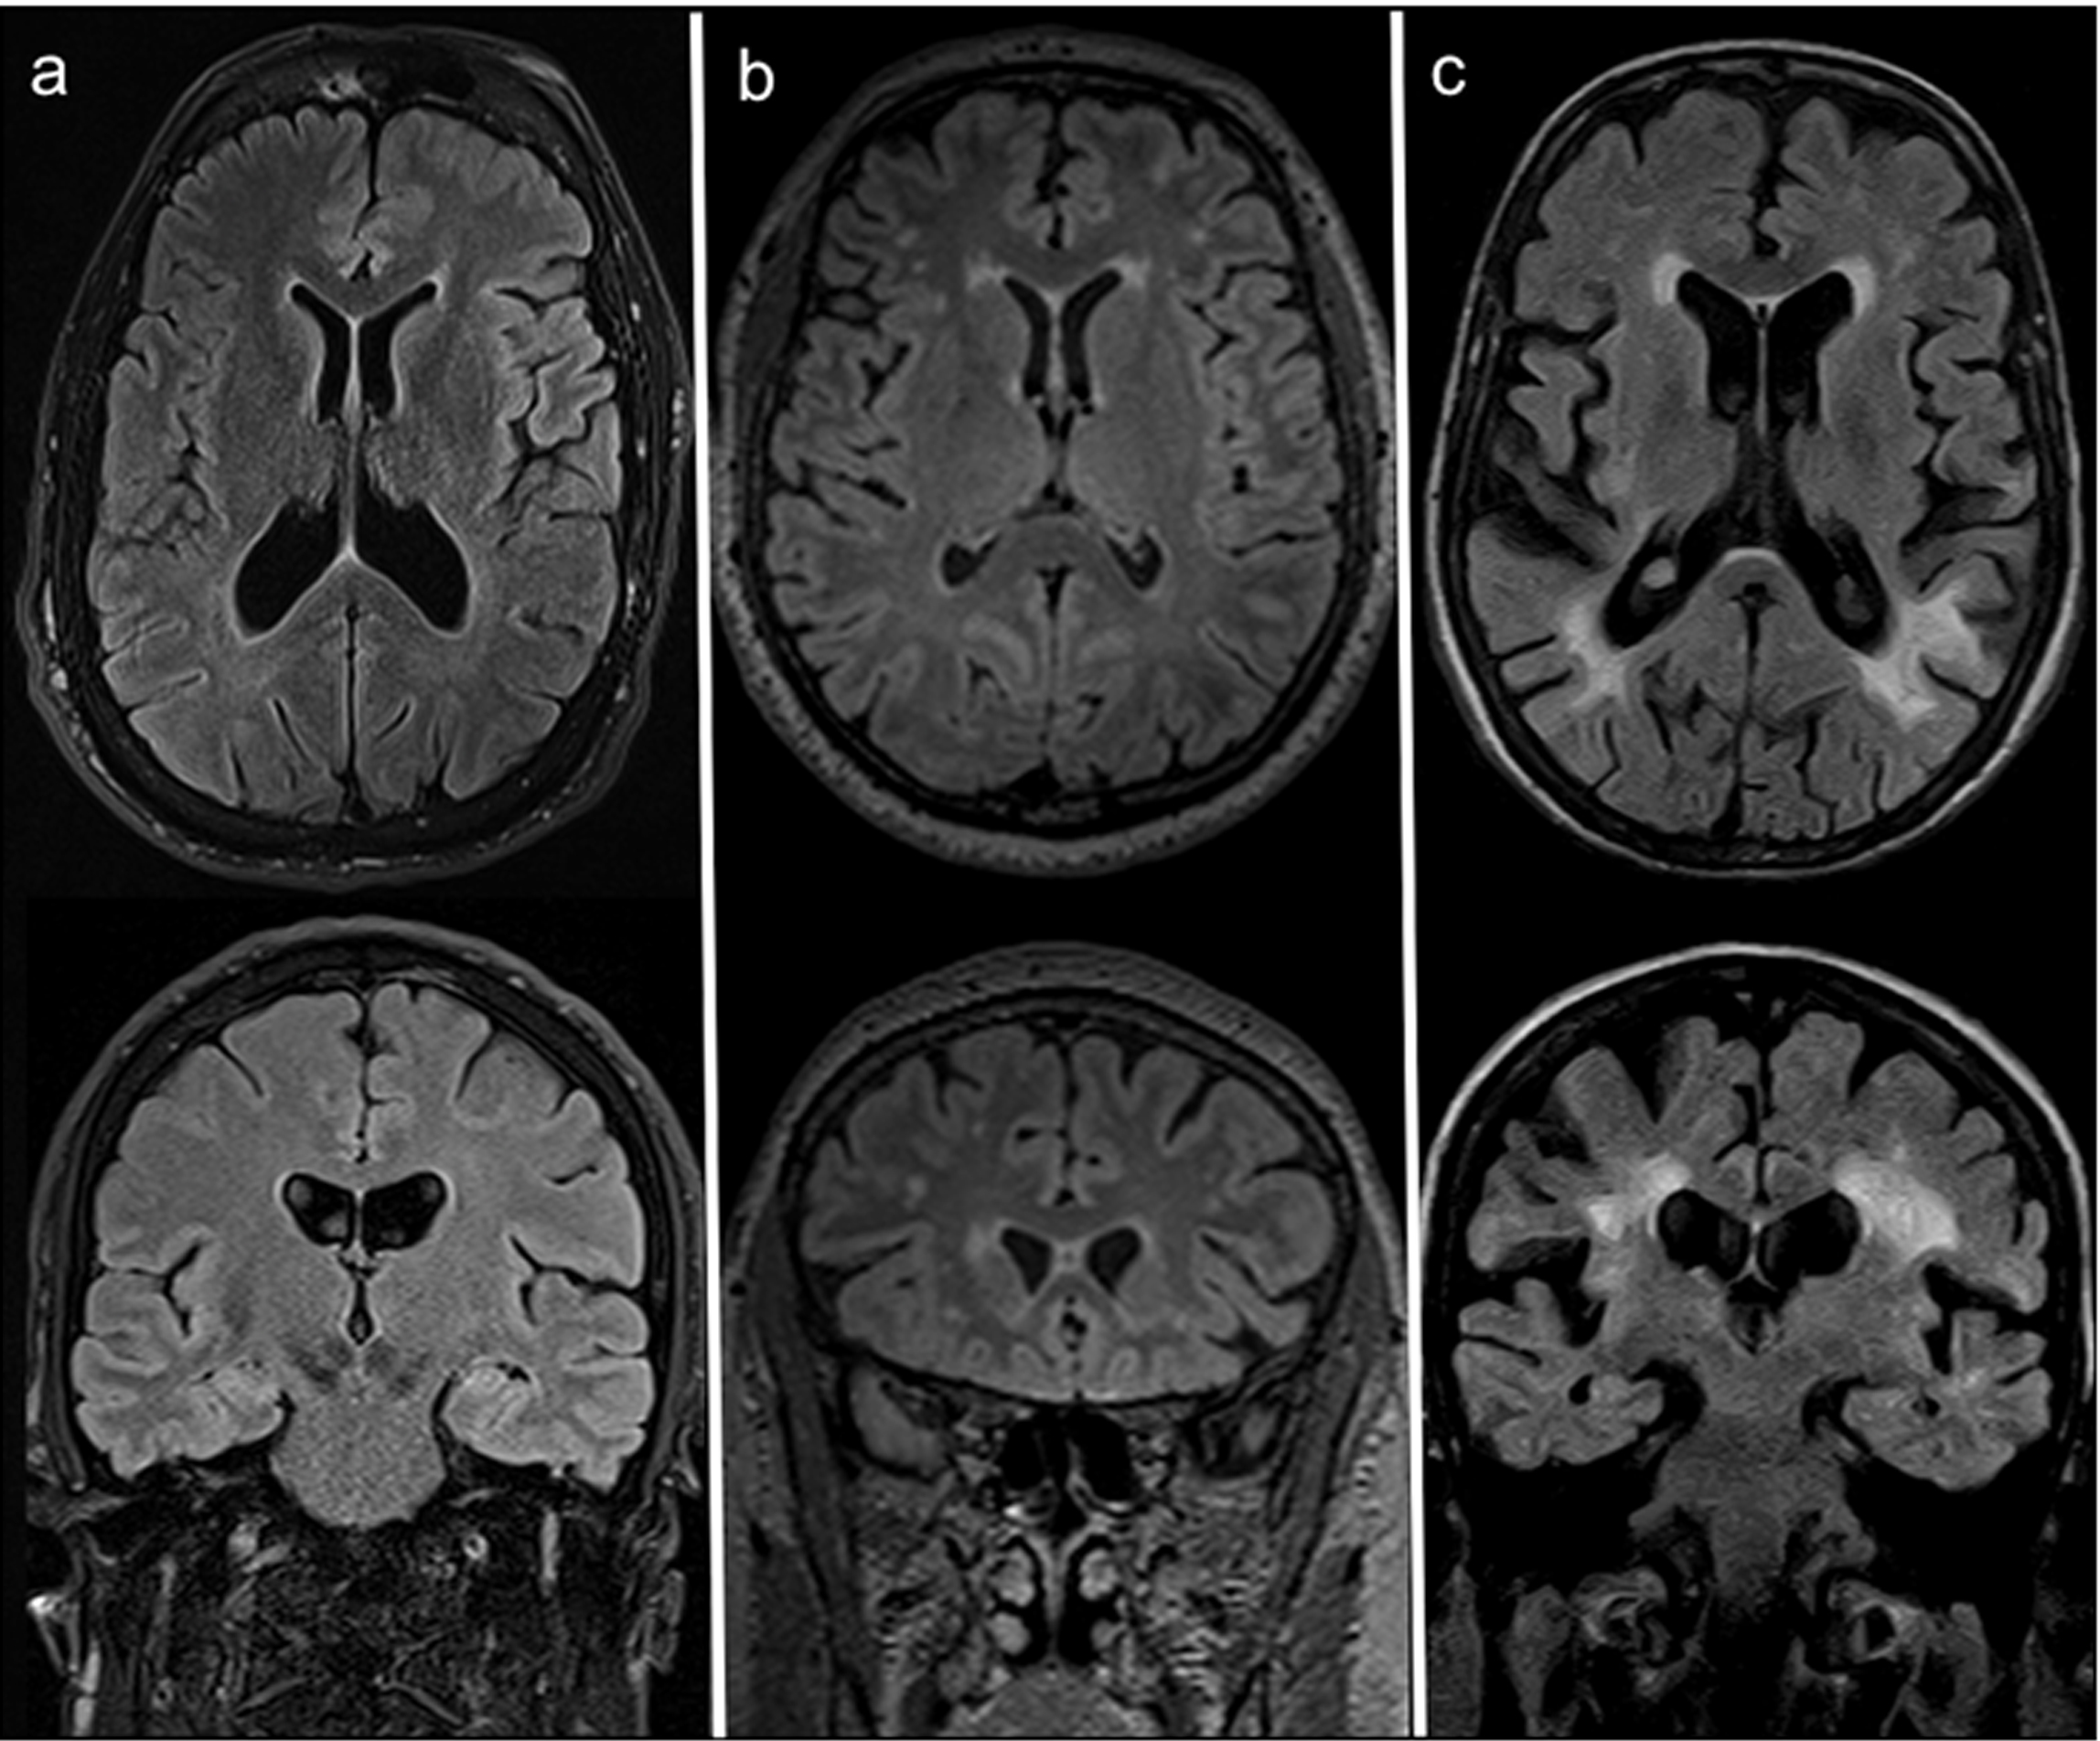

Small silent ischemic lacunae, when present, were considered as part of the white matter hyperintensity. The overall score was then calculated as the sum of the deep white matter and the periventricular white matter values [9, 27]. Figure 2 shows AFD patients with different degrees of white matter damage.

Figure 2: Axial (top) and coronal (bottom) FLAIR MRI at the most representative levels of three AFD patients with different degrees of white matter damage, respectively: (a) no WM involvement (52 years old woman with FS=0); (b) moderate WML load (44 years old male patients scoring a FS=3, with punctate foci of hyperintensity affecting the deep WM and smooth bilateral periventricular “halo”); (c) high WML load (59 years old man scoring FS=6, with largely confluent asymmetrical WMLs irregularly extending from periventricular to deep white matter and some scattered lacunar infarcts).